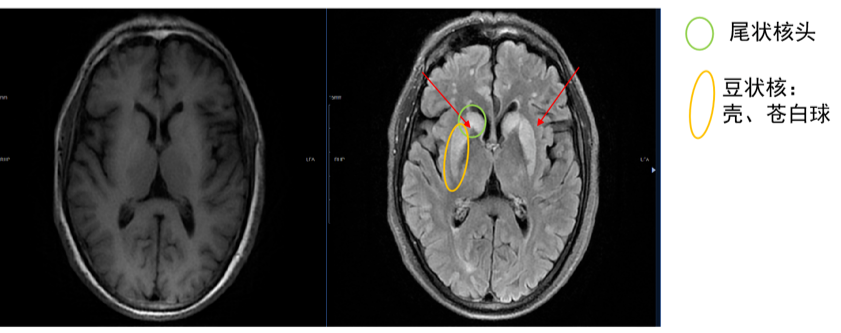

第二次住院情况(2023.08.22至2023.09.05):2月前患者食用鱼汤(量约100 mL)和瘦猪肉(量不详)后出现意识障碍,呼之不应等症状,急诊查血氨升高,考虑“肝性脑病”收治入院,入院后完善相关化验检查:血常规、肝肾功能轻度异常,颅脑MR(2023.09.03)T2WI上双重尾状核、壳核高信号,考虑高氨性脑病(急性HE或HE A型),为氨毒性所致脑水肿(图1)。予降血氨、护肝治疗,好转出院。

图1. 颅脑MR平扫的T1WI(左)和T2-FLAIR(右)序列。T1WI上双侧基底节未见高信号;T2-FLAIR上双侧尾状核和壳核见对称性高信号,考虑高氨血症对大脑的直接毒性作用,引起渗透失衡,从而出现对称性脑水肿

(源自讲者幻灯)